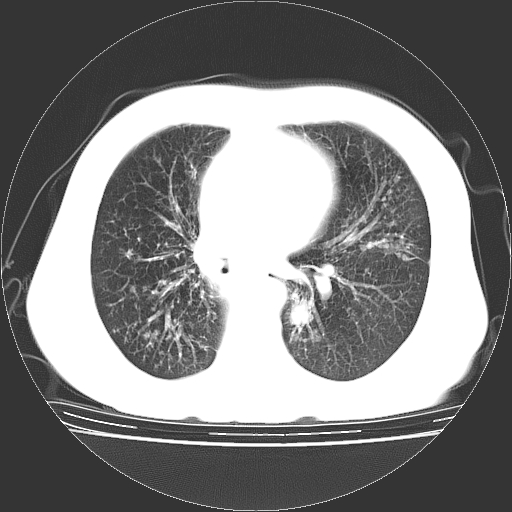

标题: CT23067:女,70岁,咳嗽、咳痰一个月,低热一周。 [打印本页]

女,70岁,咳嗽、咳痰一个月,低热一周。

1.左上肺结核,部分纤维化。右肺中下叶部分肺不张,内见液化、坏死及点状钙化,右中下叶支气管壁增厚、管腔狭窄,见多个点状钙化,结合临床考虑支气管内膜结核,建议痰检查抗酸杆菌并参考血沉。两肺多个小圆点状高密度灶,境界模糊,多考虑结核肺内播散。但本人年龄较大首先应支气管镜检以除外右肺癌。

1、右肺占位,考虑周围型ca 。

2、右下肺软组织密度肿块影,考虑肺隔离征。

右中下叶开口处结节影 所以右肺下叶癌可能性大 不除外癌性淋巴管炎